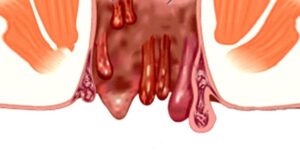

Что такое анальная бахромка, откуда появляется, как удаляется?

Анальные фимбрии — это чисто косметический дефект в виде кожных наростов вокруг анального отверстия. Они возникают в результате постоянного растяжения кожи при длительном хроническом геморрое. Анальные фимбрии, осложненные тромбозом. Причины появления анальных бахромок Суть в нарушении сократимости дермы и образовании на этом фоне свисающих кожных складок. Причин несколько: в первую очередь, внешний геморрой, затяжные роды …